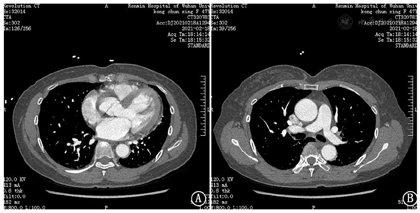

超敏肌钙蛋白I:0.103 ng/mL;胸痛三联CTA示:1.主动脉未见明显狭窄、夹层及动脉瘤征象;2.肺动脉未见明显栓塞;3.右冠状动脉起于左窦,近段纤细;左冠前降支近段非钙化斑块,管腔轻度狭窄(图2)。

本例患者首诊行急诊胸痛三联CTA检查除外了主动脉夹层、肺动脉栓塞,但冠状动脉存在一定异常,结合心电图及血清酶学表现,临床初步诊断考虑为急性冠脉综合征。入院后超声心动图提示主动脉瓣中-重度关闭不全及主动脉窦部夹层,对CTA进行复片提示主动脉根部伪影,仍不支持主动脉夹层诊断,但外科术中证实为主动脉窦部夹层。CTA漏诊主动脉窦部夹层的原因可能是:1、CTA检查易受心脏运动产生的图像伪影影响,且伪影多发生于主动脉近端,本例患者主动脉夹层撕裂内膜局限于主动脉窦部,恰好位于CTA伪影多发部位,造成CTA结果判断偏差;2、尽管胸痛三联CTA是实现胸痛一站式诊断的首选检查,但存在充分显示冠状动脉、肺动脉及主动脉的CTA增强目标各不相同的缺陷[3],理论上如果三个血管都显影意味着与此同时四个心腔里都会被造影剂填充,浓度过高的造影剂就会导致硬化线束伪影的产生,从而影响特别是右冠和肺动脉起始部位的观察,本例患者CTA见升主动脉根部见线样低密度影,延伸至腔外,故放射科医师根据经验判断为主动脉根部伪影,导致主动脉窦部夹层漏诊。